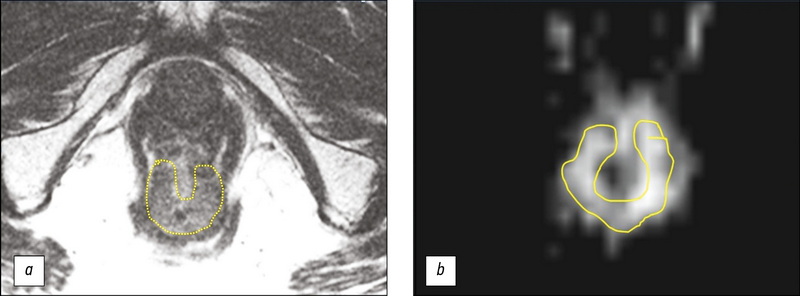

MRI评价1例直肠癌新辅助放化疗结果,辅以肿瘤T2WI结构分析(临床病例)

本文报告一名对新辅助化疗有良好反应的73岁下段壶腹直肠癌患者,采用积极动态随访策略(Watch & Wait策略)的临床病例。经过三年的定期随访,包括指状直肠检查、直肠镜检查和磁共振成像(MRI),表明肿瘤没有进展,得到了18F氟脱氧葡萄糖正电子发射断层摄影与计算机断层摄影的结果。结果显示直肠下段壶腹部有一个高代谢活动的部位(SUVmax 27.1),因此决定进行手术治疗。讨论手术范围时,考虑MRI资料,辅以T2WI分析结果,证实无疾病进展。患者接受了保留器官的经肛门肿瘤切除体积的治疗。手术准备的病理形态学检查确定了肠壁炎症改变和肿瘤的消失。本案例证明了标准调查体积在使用Watch & Wait策略时的有效性,以及使用T2WI分析来提高MRI评估肿瘤对放化疗反应的可靠性的可能性。